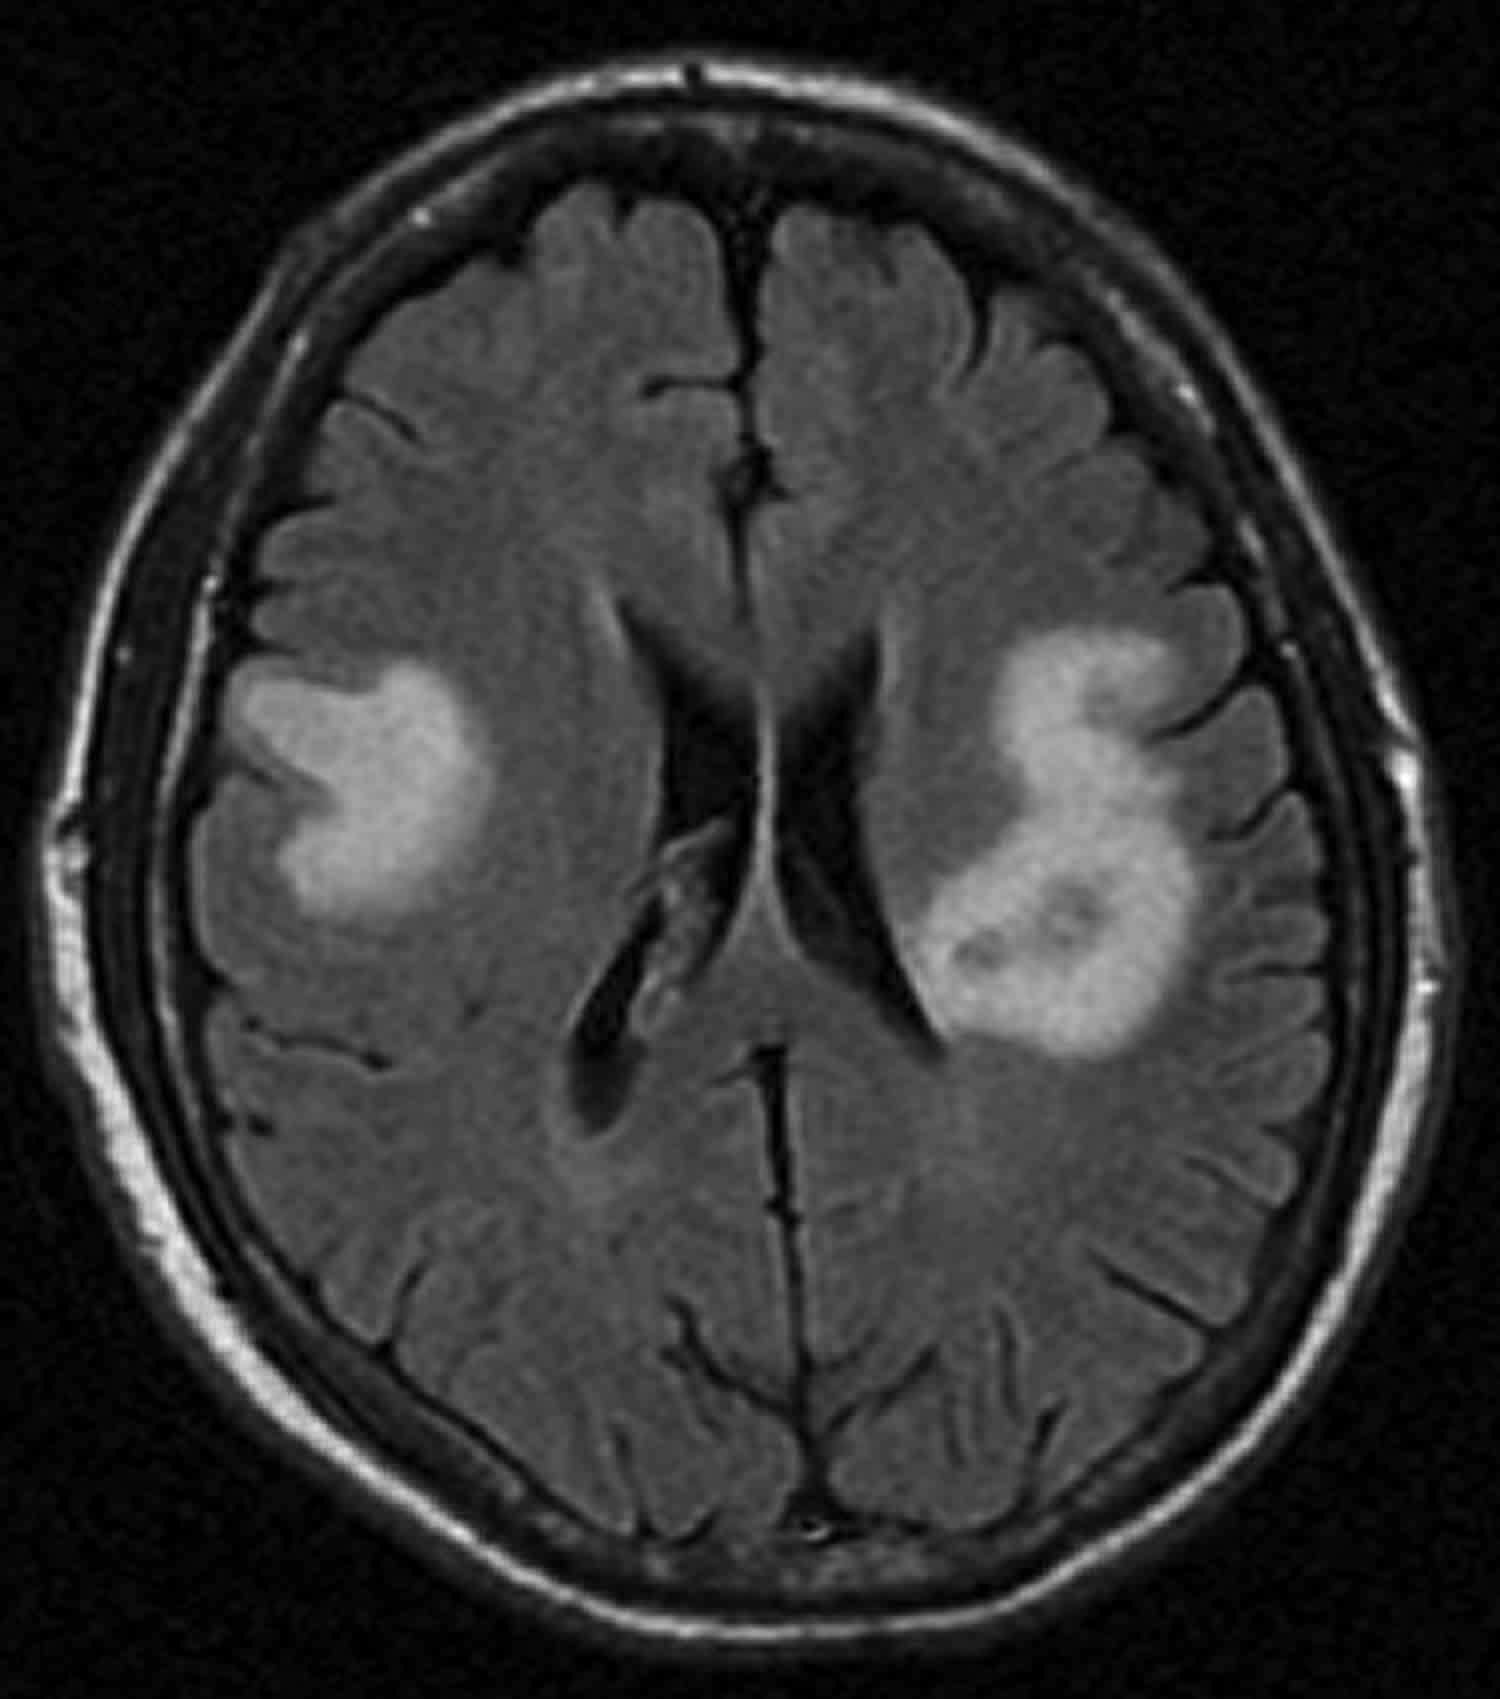

Abcesul la creier este o afecțiune serioasă și poate fi asociat cu o gamă largă de cauze, inclusiv infecții provenite din alte părți ale corpului.